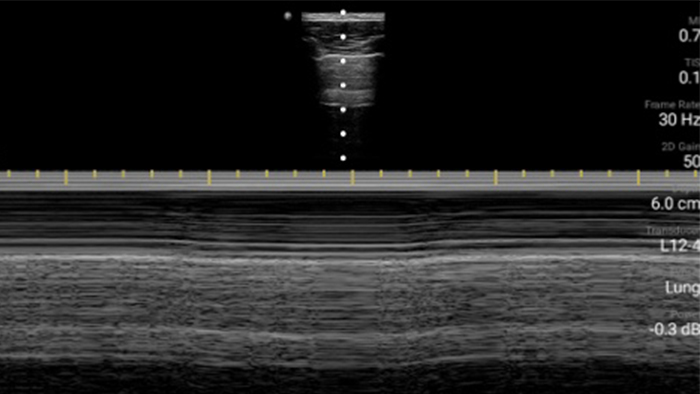

Lumify L12-4 broadband linear array transducer

• 5 to 2 MHz extended operating frequency range • 50mm radius of curvature • 2D, color Doppler, M-mode, advanced XRES and multivariate harmonic imaging, SonoCT • High-resolution imaging for deeper applications: abdominal, gall bladder, OB/GYN and lung imaging preset optimizations